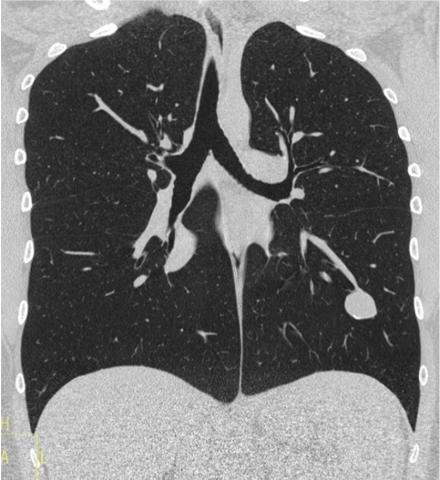

Entraînez-vous à lire des radios en vous appuyant sur des corrélations radio-scanner! Découvrez le site d'auto-apprentissage de la radiographie thoracique